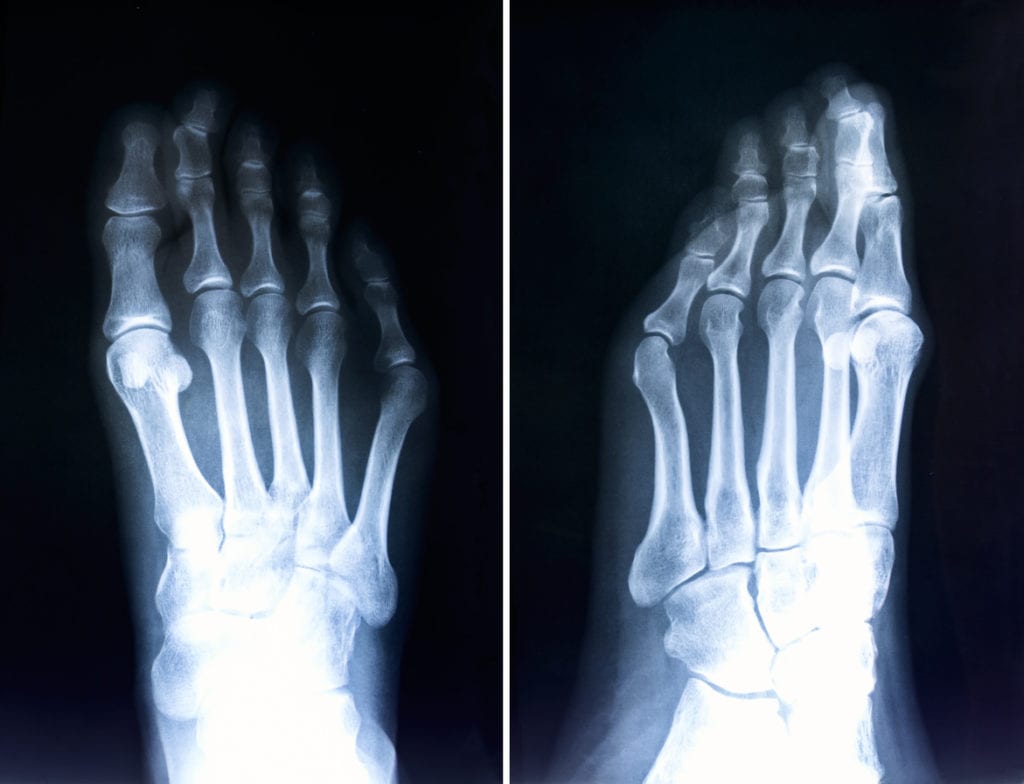

Bunions

Bunions are hard bumps that form over time at the upper, inside region of your foot, right below the big toe. Bunions tend to cause discomfort, as rubbing against the inside of your shoes can cause blisters or calluses. Because the misalignment is at the base of the body (your feet), the improper distribution of weight when you walk can cause unnatural pressure on unintended areas of the foot. Like hammertoe, claw toe, and mallet toe, bunions can form as a result of genetics, but impractical footwear can also cause and exacerbate the problem.